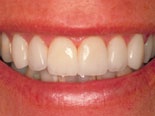

Fyra keramiska skalfasader före och efter behandling - sett från sidan.